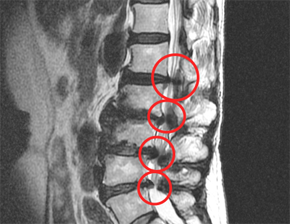

협착증 환자는 척추관을 둘러싼 그 부근 전체, 뼈, 인대, 후관절, 디스크 등이 깡그리 으로 퇴보되어 두꺼워지므로 다리로 가는 신경이 눌려서 근력이 약화되고 근육이 위축됩니다.

퇴행으로 기인해서 뼈도 골극이 자라 두꺼워지고, 후관절도 두꺼워지고, 척추관 안에 있는 인대도 두꺼워지고, 앞에 있는 디스크도 수분이 빠져 납작해지면서 척추관 공간 안을 좁게 만들고요. 이렇듯 척추관을 둘러싼 근처 전체가 다 두꺼워지고 해서 척추관이 좁아질 수밖에 없는데요.

그리고 척추관이 좁아지니까 그 가운데의 신경이 압박되어 신경성 파행, 즉 걸음을 걸으면 다리가 아픈 증상이 나타나게 됩니다.